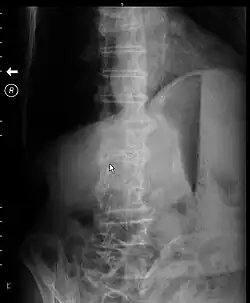

X-ray of abdomen of a person with gastric outlet obstruction taken while on their side. There is a prominent gastric air bubble, gastric air-fluid level, and a dilated stomach with particulate matter within it. | |

Abdominal X-ray may show a gastric fluid level which would support the diagnosis.